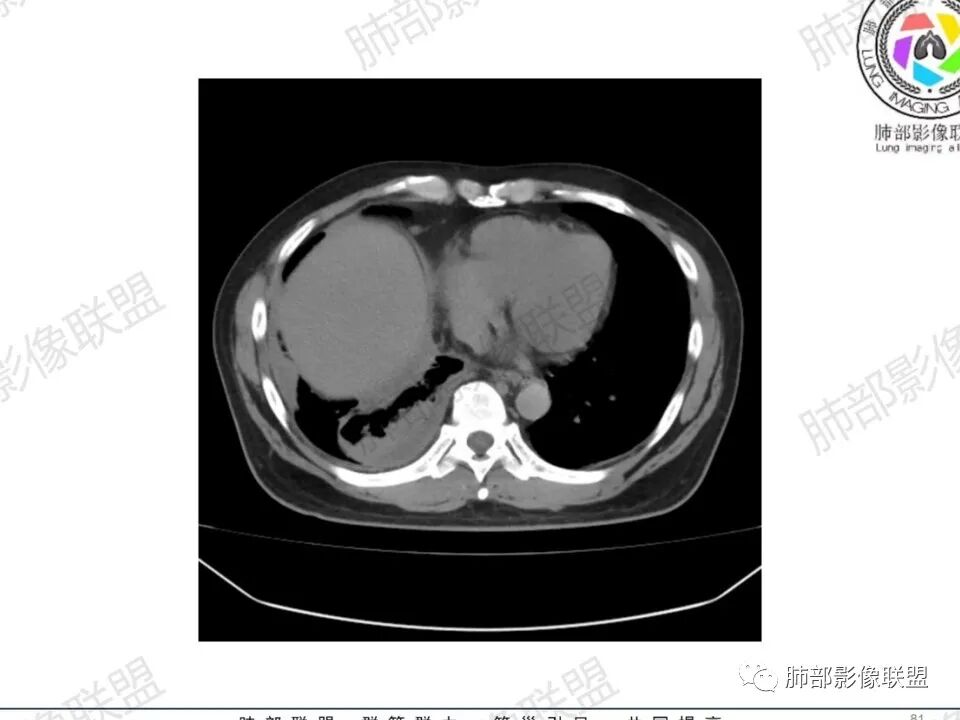

双肺多发结节,胸膜下为主,部分可见空洞。左肺上叶尖后段结节较大,分叶毛刺,周围可见长条索及小斑片影,内空洞比较光滑,内侧壁可见支气管通过。右肺下叶后基底段不张实变,后侧积液,右侧水平裂积液,右侧膈胸膜纵膈胸膜增厚积液,右侧侧胸膜肥厚,考虑1:一元金葡。2二元:金葡,左肺上叶结核。

感觉还是金葡入血形成SPE可能性较大,胸水+楔形影+胸膜结节

King: 首先肯定存在血播spe,金葡可能大。其次注意右侧包裹的胸水和肺不张,结核常见,可能二元,金葡是否常见包裹待商榷。

中年男性,左手中指及胸壁疼痛伴发热来诊,影像见双肺多发结节,胸膜下分布为主,部分结节可见空洞,边缘模糊。左肺上叶尖后段结节较大。右肺下叶后基底段不张实变,右侧叶间裂及右侧胸腔积液,右侧侧胸膜肥厚。考虑金葡菌感染,血播SPE。

有胸腔积液更提示血道来源

胸水,部分包裹

支持血道来源感染性病变,金葡菌肺炎首选

一般包裹提示粘连,多为炎性改变

脓胸也可以